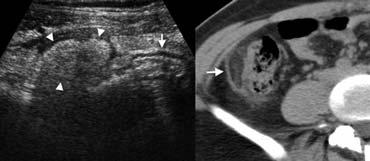

Hình 7. Nữ giới 29 tuổi bị viêm túi mỡ đại tràng. A, Siêu âm hố chậu phải cho thấy một khối mỡ viêm tăng âm (đầu mũi tên) kề cạnh đại tràng (mũi tên), tại vị trí đau tối đa. B, Trên CT không tiêm thuốc cản quang, tổn thương mỡ chứa một vòng tăng tỷ trọng đặc trưng (mũi tên) tương ứng với lớp phúc mạc tạng dày lên.

Viêm túi mỡ đại tràng

Các túi mỡ đại tràng là những cấu trúc mỡ nhỏ nhô ra từ bề mặt thanh mạc của đại tràng. Một túi mỡ đại tràng có thể bị xoắn và viêm thứ phát, gây đau bụng khu trú giống viêm ruột thừa khi nằm ở hố chậu phải.

Viêm túi mỡ đại tràng là bệnh tự giới hạn, được báo cáo ở khoảng 1% bệnh nhân có nghi ngờ lâm sàng viêm ruột thừa [5].

Siêu âm và CT cho thấy một khối mỡ viêm kề cạnh đại tràng (Hình 7), chứa một vòng tăng tỷ trọng đặc trưng của lớp phúc mạc tạng dày lên trên CT [5].